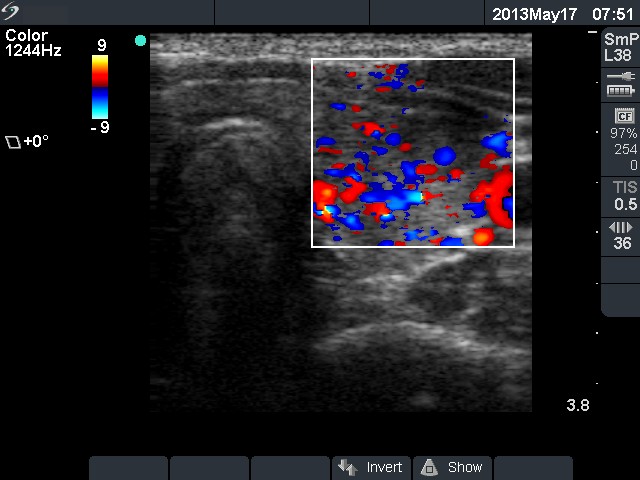

100 consecutive cases of papillary cancer - case 035

Three years prior to present examination (ultrasonographic picture 6)

Left lobe, transverse scan, color Doppler mode. The vascularization is increased.